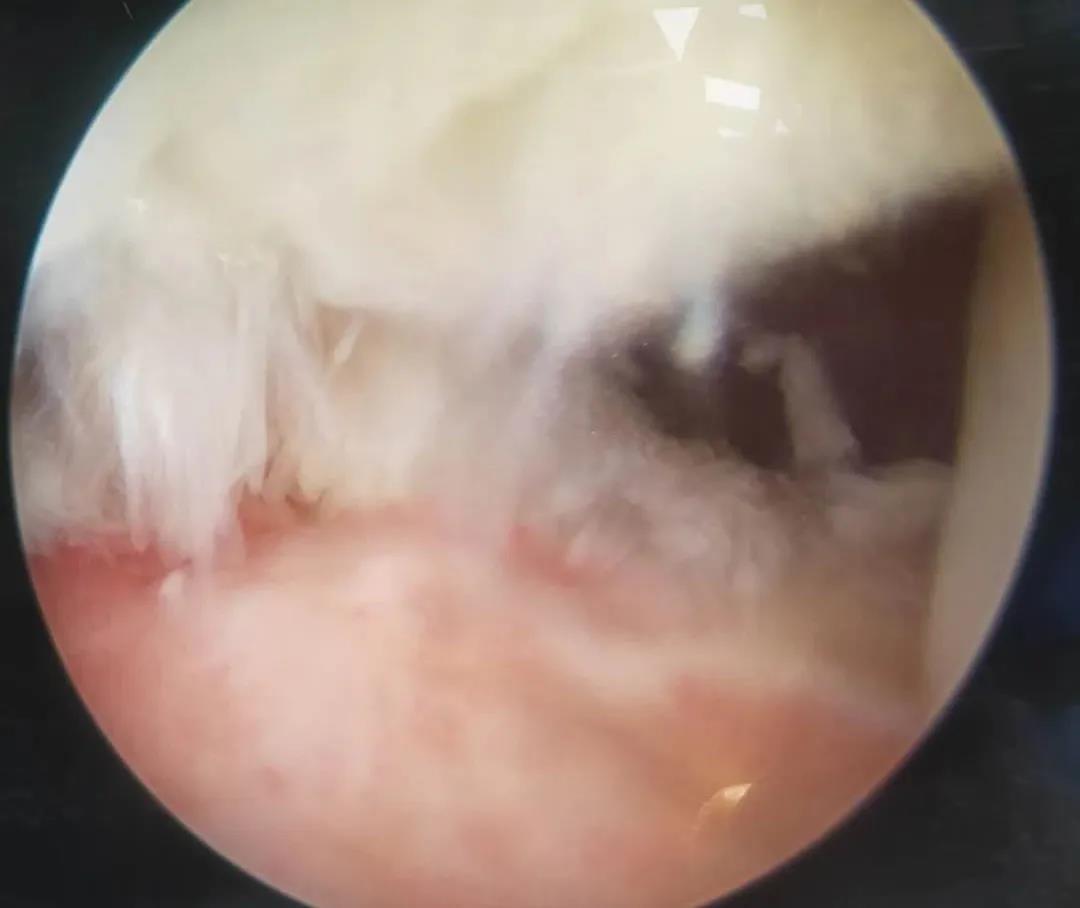

膝關(guān)節(jié)半月板損傷和前后交叉韌帶損傷是運(yùn)動損傷常見疾病,半月板損傷后不能自行愈合,盡早手術(shù)可以避免繼發(fā)關(guān)節(jié)軟骨的損傷,骨二科采用關(guān)節(jié)鏡下半月板縫合手術(shù),能少切除就少切除,能縫合盡量縫合,最大努力保留患者半月板,更好的恢復(fù)膝關(guān)節(jié)的功能。膝關(guān)節(jié)前后交叉韌帶損傷一般采用單束重建,只能恢復(fù)原來韌帶的80%的強(qiáng)度,骨二科采用雙束重建,能夠比原來的韌帶更粗更強(qiáng),為后期的功能鍛煉及恢復(fù)提供良好的基礎(chǔ)。

關(guān)節(jié)鏡下雙束重建